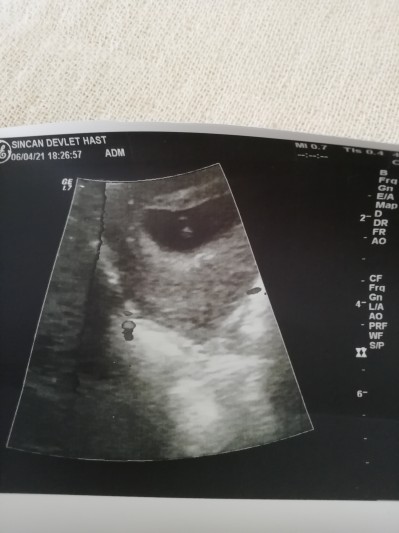

Arkadaşlar 5 haftalık hamileyim detaylı ultrason çekindim resimde ikiz gibi farkettim doktor bişey söylemedi ama sizce fikri olan var mı

Gebelik haftası 5

Canım 1 tane kese var resmin üst tarfinda yani hani nerde ikinci kese göremedim ben.

Aynı kesenin içinde de olma ihtimali olabiliyor muş orda sanki var gibi gördüm yada öyle görmek istedim

Kesenin içindeki iki tane çizgi görünüyor fakat birisi bebek birisi eşi olabilir. Yada osta kısma amniyon sıvı fazla geldiği için siyah olmuş olabilir. İkiz olsaydı mutlaka doktor söylerdi. Tek kalp atışı mi dinledi